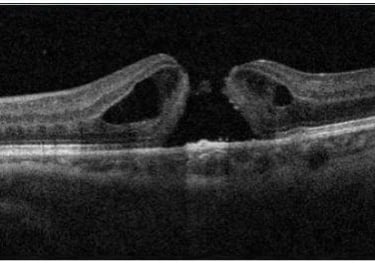

Degeneração Macular Relacionada a Idade (DMRI)